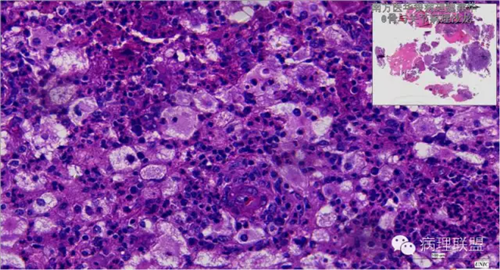

来源于组织细胞的相似性骨病ECD vs RDD 看图说话

病例由南方医华银病理魏建华提供,致谢。